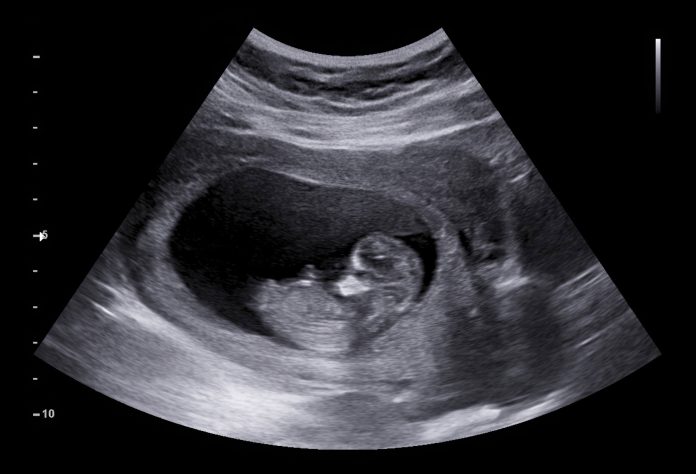

Το πρώτο υπερηχογράφημα της εγκυμοσύνης. Το υπερηχογράφημα αρχόμενης κύησης και βιωσιμότητας του εμβρύου που γίνεται στην έγκυο

Υπερηχογράφημα εγκυμοσύνης πρώτου τριμήνου

Το υπερηχογράφημα αυτό πραγματοποιείται, συνήθως, μεταξύ 6ης και 10ης εβδομάδας κύησης διακολπικά ή καλύτερα διακοιλιακά.

Στην εξέταση αυτή ελέγχεται, αρχικά, εάν το κύημα αναπτύσσεται μέσα στη μήτρα (ενδομήτρια εγκυμοσύνη) και ακούτε τους χτύπους της καρδιάς του εμβρύου.

Ελέγχετε τον αριθμό των εμβρύων εντός της μήτρας (μονήρης ή πολύδυμη κύηση).

Στη συνέχεια ελέγχεται η ανάπτυξη του εμβρύου, επιβεβαιώνεται, δηλαδή, πως το έμβρυο μεγαλώνει σύμφωνα με την ηλικία της κύησης. Σε περιπτώσεις όπου η μητέρα δε θυμάται την πρώτη ημέρα της τελευταίας περιόδου, είχε ασταθή κύκλο ή ήταν υπό αντισυλληπτική αγωγή ή θήλαζε προσδιορίζεται τόσο η ηλικία της κύησης όσο και η πιθανή ημερομηνία του τοκετού μετρώντας το μήκος του εμβρύου (κεφαλουραίο μήκος).